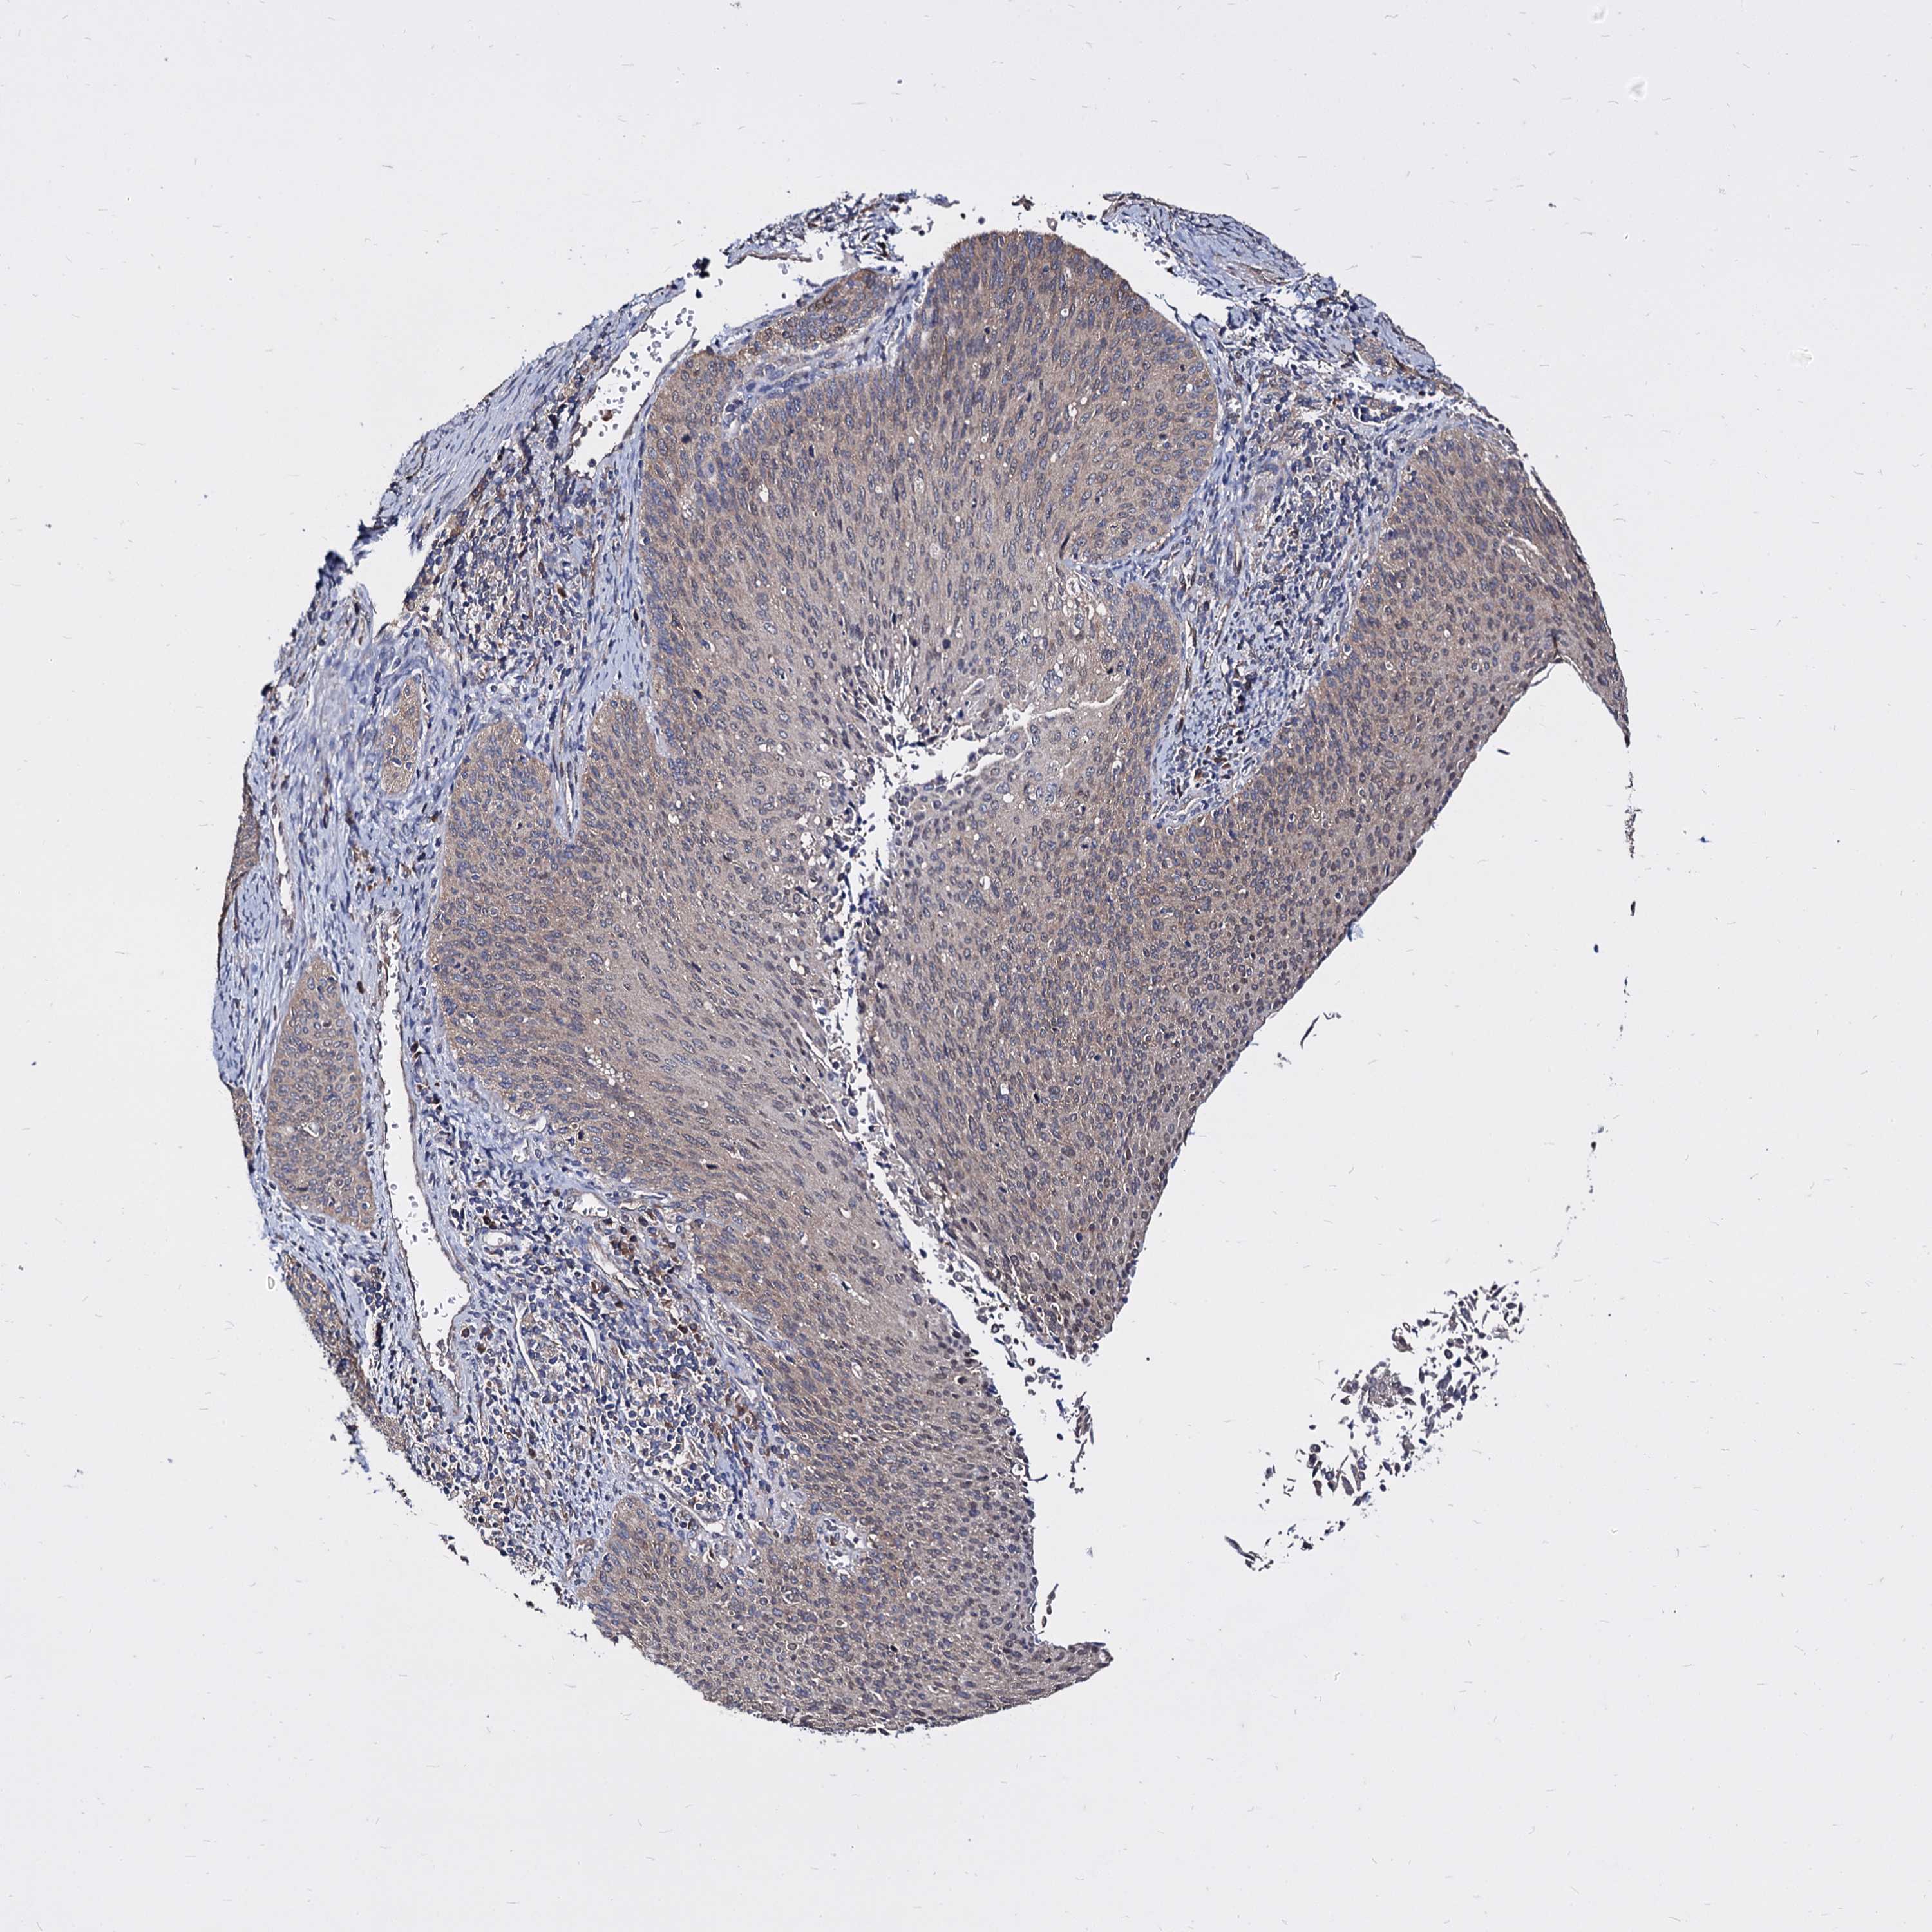

CERVICAL CANCER - Protein expressioni

A mouse-over function shows sample information and annotation data. Click on an image to view it in a full screen mode. Samples can be filtered based on level of antibody staining by selecting one or several of the following categories: high, medium, low and not detected. The assay and annotation is described here.

Note that samples used for immunohistochemistry by the Human Protein Atlas do not correspond to samples in the TCGA dataset.

Antibody stainingi

Antibody staining in the annotated cell types in the current human tissue is reported as not detected, low, medium, or high, based on conventional immunohistochemistry profiling in selected tissues. This score is based on the combination of the staining intensity and fraction of stained cells.

Each image is clickable and will lead to virtual microscopy that enables deeper exploration of all samples and also displays staining intensity scores, fraction scores and subcellular localization as well as patient and tissue information for each sample.

HPA008467

HPA041113

CAB040571

CAB080149

CAB080151

CAB080152

Staining

High

Medium

Low

Not detected

Intensity

Strong

Moderate

Weak

Negative

Quantity

>75%

75%-25%

<25%

None

Location

Nuclear

Cytoplasmic/membranous

Cytoplasmic/membranous,nuclear

Squamous cell carcinoma, NOS

Adenocarcinoma, NOS